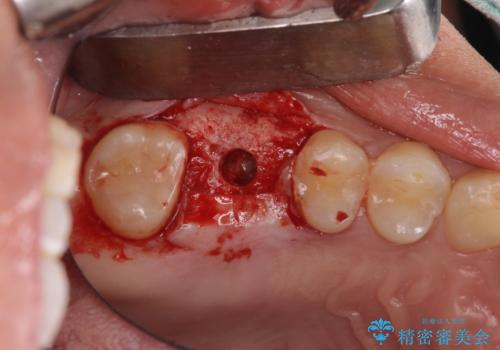

- 深い咬み合わせと前歯のデコボコ、奥歯の欠損を気にして来院された患者様です。

歯列矯正はインビザラインを使用し、矯正治療中の適切な時期に奥歯の欠損部位にインプラントを埋入することとしました。

矯正治療とインプラント治療を同じ歯科医師が担当することで、通常見られるような複数医院を行き来する煩雑さや、複数担当医の見解の違いによる治療の遅滞といった煩わしさは一切なく、スムーズに治療を進めることができました。